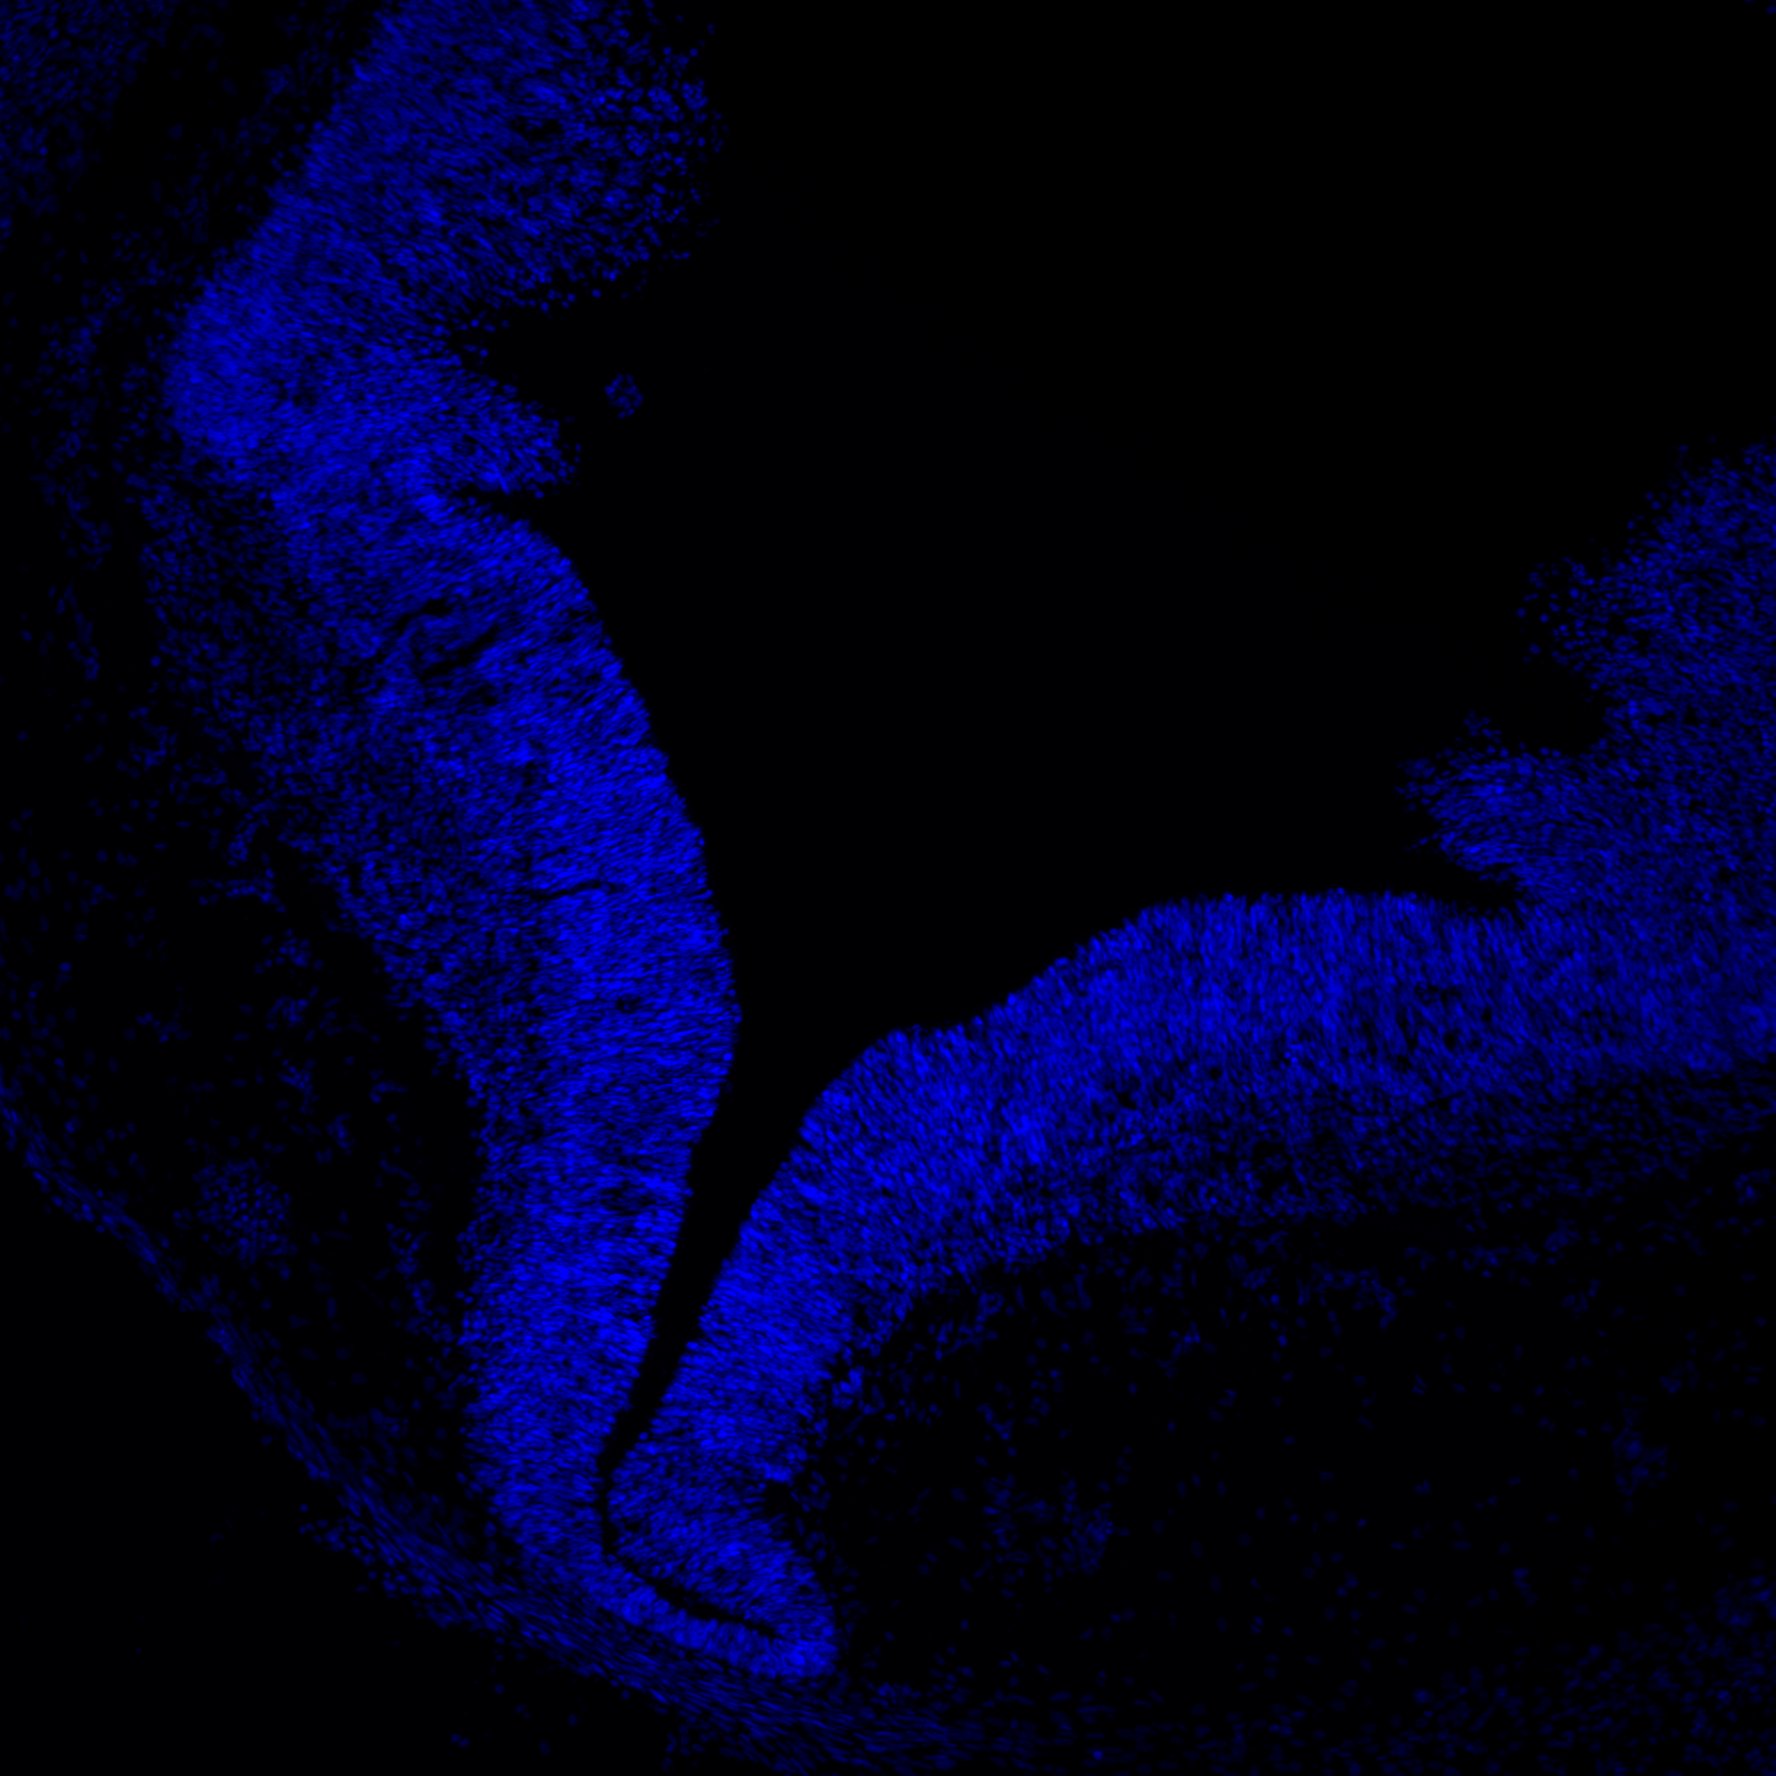

DAPI

6PCW human midbrain